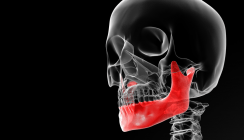

Bei der Extraktionsbehandlung muss die gleiche Differentialdiagnose verwendet werden wie bei der Non-Extraktionsbehandlung. Bei der Extraktionsbehandlung können zwei zusätzliche mechanische Verfahren helfen, den frontal offenen Biss zu schließen; diese sind das Zugbrücken-Prinzip und die Mesialisation der posterioren Zähne.2,13 In einigen Fällen sind die Frontzähne labial geneigt, sodass eine Retraktion der vorderen Zähne diesen Zähnen ermöglicht, sich lingual zu neigen, was einer Zugbrücke ähnelt (Abb. 8). Mit diesem Verfahren kann der frontal offene Biss reduziert werden, ohne die Frontzähne zu extrudieren. Wenn der offene Biss stark ausgeprägt ist, wird der Abschluss mithilfe intermaxillärer frontaler Gummizüge erreicht. In vielen Fällen kann durch eine Extraktion den posterioren Zähnen ermöglicht werden, bis zu einem gewissen Grad zu mesialisieren. Dieses Verfahren ermöglicht eventuell eine gewisse mandibuläre Rotation gegen den Uhrzeigersinn oder verhindert zumindest eine Rotation im Uhrzeigersinn, was die Korrektur des offenen Bisses unterstützt (Abb. 9).

Die klinische Stabilität von Extraktionsfällen, die durch Extrusion der Frontzähne mithilfe intermaxillärer vertikaler Gummizüge behandelt werden, unterstützt bzw. nicht unterstützt durch das Zugbrückenprinzip und/oder die Mesialisierung der posterioren Zähne, beträgt 74,2 %.7 Wie auch bei der Non-Extraktionsbehandlung wurde diese klinische Stabilität jedoch bei Patienten erreicht, bei denen keine Bemühungen erfolgten, den Überbiss überzukorrigieren oder die posterioren Zähne absichtlich aufzurichten. Es wurden keine aktive Retention oder gleichzeitige Gaumenklammern oder Zungensporne verwendet; zudem wurde eine Muskelfunktionstherapie nicht beurteilt. Daher können die gleichen mechanischen Strategien, die bei der Non-Extraktionsbehandlung verwendet werden, bei der Extraktionsbehandlung verwendet werden, um dieses Ausmaß der klinischen Stabilität zu verbessern. Behandlung mittels Instrusion der posterioren Zähne Wenn die Differentialdiagnose eine normale bis übermäßige Freilegung der oberen Schneidezähne beim Lächeln zeigt, muss die Behandlung mittels Intrusion der posterioren Zähne erfolgen.4,8 Die Intrusion der posterioren Zähne ermöglicht eine mandibuläre Rotation gegen den Uhrzeigersinn, und der frontal offene Biss wird geschlossen (Abb. 10). Die Behandlung kann entweder mit oder ohne Extraktion erfolgen, abhängig von den üblichen diagnostischen Faktoren wie dem Ausmaß des Engstands, der Protrusion der Frontzähne, der Schwere des offenen Bisses und der Gesichtsstruktur, um hier nur die wichtigsten zu nennen.3,13 Eine Molarenintrusion zeigt eine Rückfallquote von 20 bis 30 %,4,8,22 was darauf hinweist, dass eine Überkorrektur in Verbindung mit den anderen bereits erwähnten Verfahren erforderlich ist.